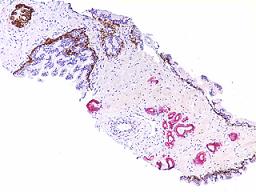

The Genitourinary (GU) pathology service at UMass Memorial Medical Center provides skilled interpretation of specimens from the prostate, urinary bladder, kidney and testis. Our GU  pathology section serves the UMass Memorial Medical Center and urology practices in Massachusetts and Connecticut. We have developed a novel molecular diagnostic technique combining cytology and fluorescent in situ hybridization (FISH) analysis, a cutting edge technology for the diagnosis of urothelial carcinoma. We utilize an array of immunohistochemical and molecular biological techniques in the evaluation of pathological diagnostic problems.

pathology section serves the UMass Memorial Medical Center and urology practices in Massachusetts and Connecticut. We have developed a novel molecular diagnostic technique combining cytology and fluorescent in situ hybridization (FISH) analysis, a cutting edge technology for the diagnosis of urothelial carcinoma. We utilize an array of immunohistochemical and molecular biological techniques in the evaluation of pathological diagnostic problems.

Our major research focus is the identification and validating novel biomarkers for diagnostic and prognostic use. Alpha-methylacyl-coenzyme A racemase (AMACR/P504S), a molecular diagnostic biomarker for prostate cancer that Dr. Jiang first described in 2001, now assists pathologists around the world accurately diagnose prostate cancer in prostate needle biopsies. Recently, we discovered IMP3, a new molecular marker that allows patients and cliniciansget an accurate prediction of the metastatic potential or progression of renal cell carcinoma and superficial bladder cancer.

Our major research focus is the identification and validating novel biomarkers for diagnostic and prognostic use. Alpha-methylacyl-coenzyme A racemase (AMACR/P504S), a molecular diagnostic biomarker for prostate cancer that Dr. Jiang first described in 2001, now assists pathologists around the world accurately diagnose prostate cancer in prostate needle biopsies. Recently, we discovered IMP3, a new molecular marker that allows patients and cliniciansget an accurate prediction of the metastatic potential or progression of renal cell carcinoma and superficial bladder cancer.